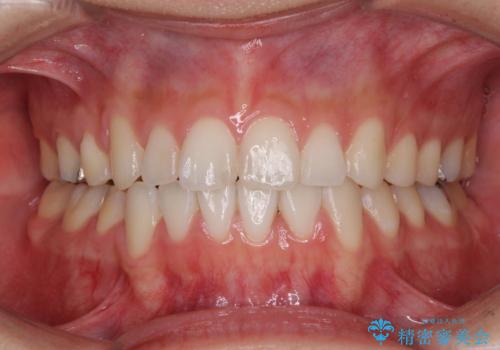

途中海外留学をされたため、治療期間は長くなりましたが、事前に補助装置やワイヤー装置を併用したことで、きれいな歯列に仕上げることができました。

上下の八重歯を治したい 補助装置を用いたインビザライン矯正